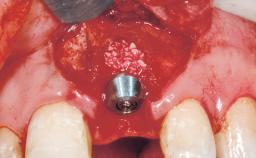

A 39-year-old male patient presented with a chief complaint of discomfort and gingival discoloration around his maxillary left central incisor. He was in good general health and was a non-smoker. His past dental history was significant because of the traumatic fracture of tooth 21 in a sporting accident at age 13. Initial dental treatment included endodontic therapy and a full-coverage restoration. The patient became symptomatic 5 years later, when structural failure of the tooth resulted in the dislodgment of the crown. Endodontic retreatment, apical surgery, and post-and-core restoration were performed.

Bone Augmentation Horizontal|Staged

Augmentation Materials Xenogenous|Membrane

Soft Tissue Grafting Simultaneous

Bone Volume Deficient horizontally, requiring prior grafting